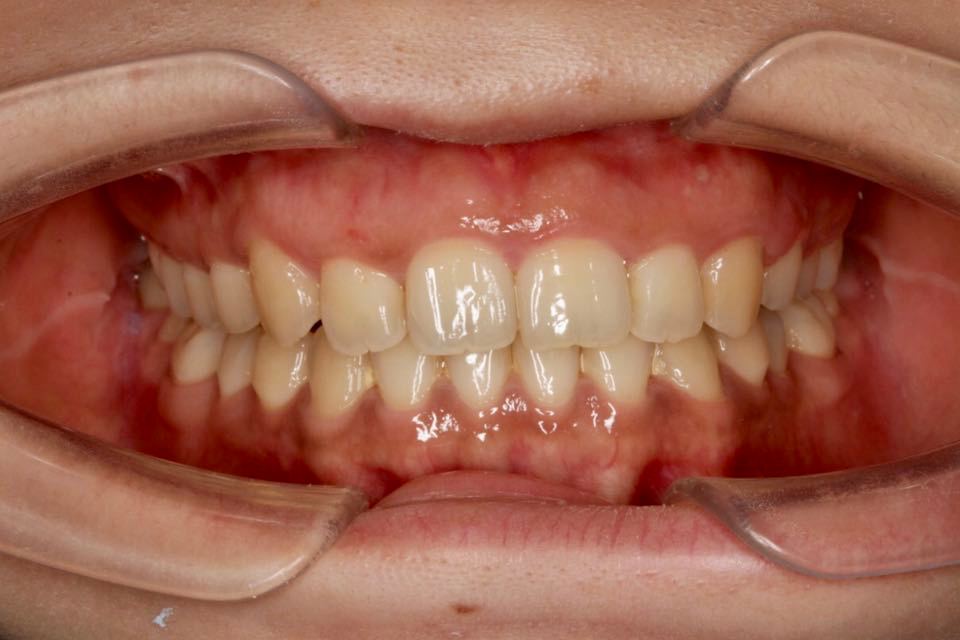

矫正前口内照:

正面观:面部左右基本对称,微笑正常。

口内:恒牙列,牙列拥挤(中度)。上下颌牙弓呈方圆型。左右对称。右侧磨牙近中性关系,左侧磨牙近中关系,右侧尖牙远中关系,左侧尖牙远牙中性关系。上颌中线偏右2mm,下中性居中。